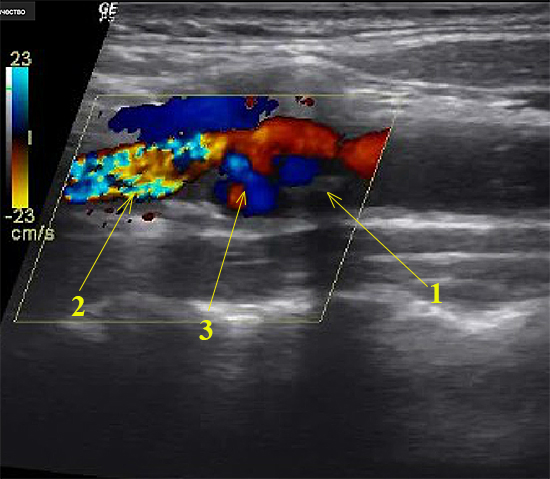

Уважаемые коллеги! Пациент М,57 лет направлен на ЦДС БЦА неврологом поликлиники по поводу ТИА,обследован впервые,курильщик,стаж курения 20 лет. В устье ВСА распространённая,полуконцентрическая (по задне-латеральной стенке,на видео поперечная позиция не представлена) протяжённостью 17 мм,гетерогенная АБ с включениями кальция,с неровной поверхностью. ЛСК в дистальном отделе ОСА 70см/сек,над АБ до 200см/сек,в проксимальном отделе ВСА 56см/сек. Моё ЗАКЛЮЧЕНИЕ: Гемодинамически значимый стеноз устья правой ВСА (70-75%) атеросклеротической бляшкой, осложнённой изъязвлением. Хотелось бы услышать мнения по поводу осложнения данной бляшки и должен ли врач УЗД предпринимать какие-либо дополнительные действия при выявлении осложнённой АБ. Спасибо!

Расслоение бляшки!

1 - Отслоение проксимальной части бляшки

2 - элайзинг на стенозе (низко выставлен скоростной предел)

3 - цветовая картина турбулентного потока

Я заметил, что скорость у вас стоит 23 см/сек., а нужно было ставить 33-40 см/сек, тогда артефакт бы и пропал и вы наверняка увидели бы картину схожую с турбулентным потоком КАК в язвенном кратере бляшки.